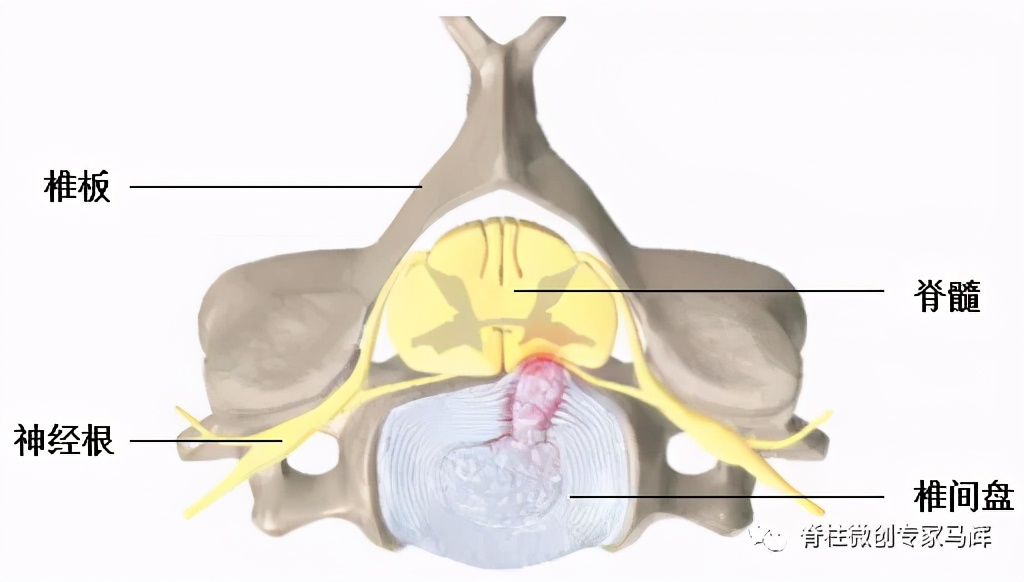

颈椎病是一种以退行性病理变化为基础,由于颈椎骨质增生,椎间盘脱出,或韧带增厚,导致颈椎脊髓、神经或血管受压,引起一系列症状的临床综合征。

颈椎微创手术创伤小、康复快,脊柱内镜可以清晰地辨别神经组织和血管等细微结构,最大限度保存了正常组织,大大降低了手术风险,特别适用于神经根型颈椎病。

神经根型颈椎病采用后路脊柱内镜手术可有效避免前路手术的一些危险并发症: